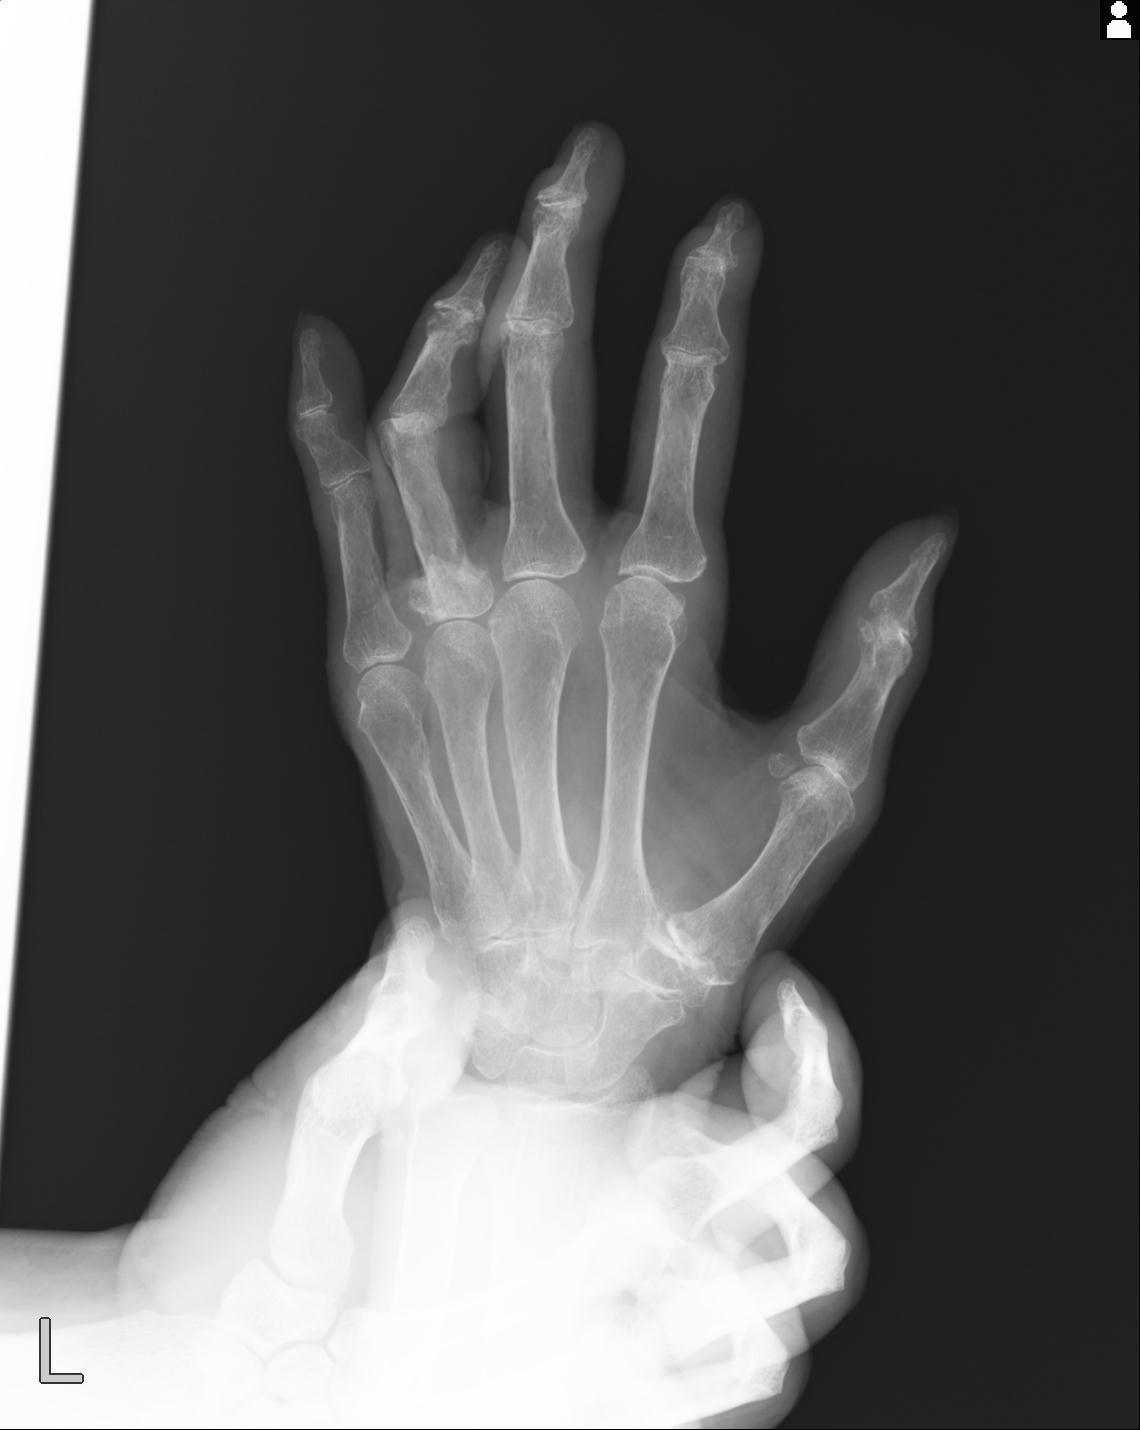

46666 1/23 両股正面+軸と右手関節 2R 76歳女性 右橈骨遠位端

46666 1/28 両股正面+軸と 1/26 右手関節 2R 76歳女性 右転子部骨折